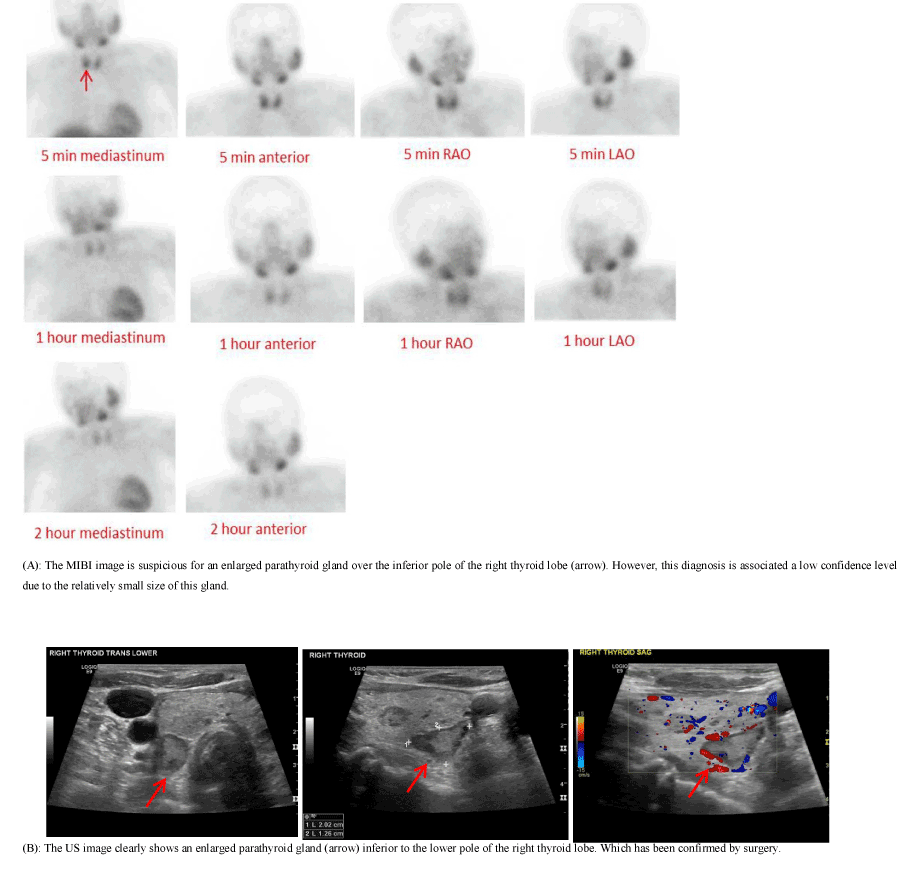

Figure 4. A 72-year-old female presented with a PTH level of 141 pg/ml and a calcium level of 10.3 mg/dl.